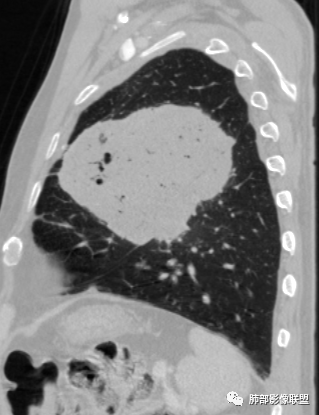

左肺上叶大肿块,膨胀性生长,边界清,密度较低,见部分坏死区,强化弱,肿块见支气管充气V扩张征,分布僵直,枯树枝特点,另一个重要特点血管造影征,淋巴瘤,肿块长轴与胸膜平行,与隐球菌鉴别,隐球荚膜抗原检查,明确诊断经皮肺穿刺。另胸膜钙化(问诊既往有无患胸膜炎病史)。

老年男性,糖尿病病史,消瘦、乏力三个月,影像表现左肺上叶胸膜下团块,有一定张力,内部疏松,可见支气管影及坏死区,增强病灶边缘环形强化,内部未见强化,考虑炎性肉芽肿病变,隐球?奴卡?放线菌?鉴别淋巴瘤。

左肺上叶胸膜下肿块,宽基底与胸膜相连,跨叶裂,边缘清晰膨隆,其内支气管充气,部分扩张、僵直,无明显强化,血管造影征,考虑淋巴瘤,鉴别腺癌

左肺胸膜下巨大占位,跨叶裂,宽基底与胸膜相连,胸膜钙化,平扫密度较低,强化不明显,可见内部血管显影,支气管充气征和扩张,考虑为恶性,倾向于淋巴瘤

我要修正一下观点了:仔细看了视频,肿块占位效应明显,对周围血管,支气管有推挤,增强后强化不明显,NSE增高,半年体重下降25公斤,虽然有内部支气管扩张,血管漂浮,边界清楚支持淋巴瘤,但强化太低,膨隆,占位推挤太明显(淋巴瘤一般没有这么明显的占位效应),胸膜关系有载桩,恶病质明显(乏力,半年体重下降了25公斤),NSE也明显增高,就不支持淋巴瘤了。还是考虑外朝内的恶性肿瘤,间质来源的肉瘤伴有神经内分泌分化或者大神泌。

不支持淋巴瘤的有四点:1、对周围血管支气管推挤明显。2、胸膜有栽桩,3、强化太弱(淋巴瘤一般还是中度以上甚至高度强化多见),4、NSE升高明显,体重下降太明显。

大肿块,边缘光滑,深分叶

近端支气管堵塞、推移为主

部分类似于脐凹征

内部支气管扩张

肺动脉推移为主,边缘部分进入

大肿块、表面光滑但深分叶,肺门侧支气管堵塞

1)部位:周围型或中央型软组织肿块,以周围型为多见,且肿瘤多位于肺上叶。如本例:该肿瘤位于左肺上叶。

2)大小及形态:由于本病恶性程度高,早期症状不明显,发现时肿块均较大。如本例病变巨大。

3)肿块边界和边缘:多较清楚,呈圆形、类圆形,且由于肿块生长速度不均匀,可见分叶,毛刺少见。有报道肿块周围毛玻璃影是多形性癌特征表现。

4)密度:肿块平扫为软组织密度,由于体积较大,内部常见大片状坏死,可出现不规则厚壁空洞或坏死内多发无壁小空洞,坏死多不均匀:坏死灶内可见如柳絮样的斑片样强化灶,坏死边缘与非坏死区分界不清本例坏死较明显,密度不均匀。

5)肿瘤强化方式:肺部恶性肿瘤强化程度与其血供丰富程度相关,血供丰富多强化明显,反之则较差。由于PSC 周边实性部分富血供及内部黏液变性、坏死,增强后肿块多数呈轻-中度边缘环形强化或不均匀小斑片状强化。国外学者对照病理发现肿瘤细胞或胶原组织增强扫描时强化,无强化的低密度区代表了黏液样变性区和出血坏死区。